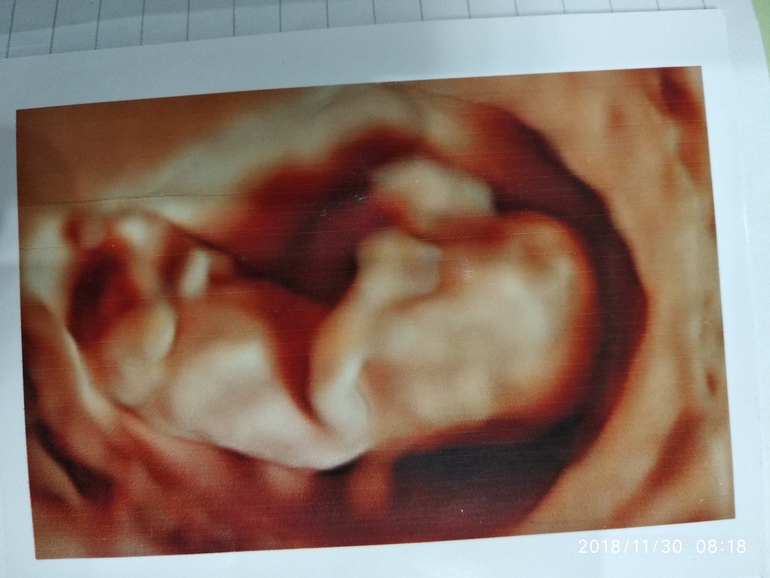

Промежуточное узи для успокоения души))фото 10 недель и 2 дня

Всё о нашей беременностиПоследний раз была на узи в 8 недель, с тех пор прошло 2 недели, не смогла утерпеть и сходила на узи посмотреть как там моя бусинка)) бусинка моя круть-верть теперь, во всю крутилась, не давалась померится. Теперь со спокойной душой можно ждать скрининг 🤗фото на память)) а вы как часто ходите на узи?))

Сверху вниз

1- 8 недель

2- 9 недель

3-10 недель

4-11н и 3д

5- 12 недель

6- 15 недель

7-16 недель

8- 20-21 неделя